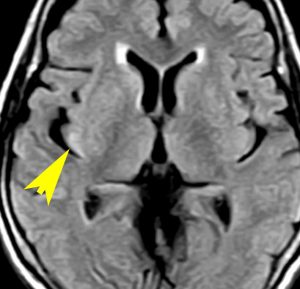

80代の女性に偶然見つかったものです。右の島のグリオーマ insular gliomaで,ガドリニウム増強されないびまん性グリオーマです。右側は2ヶ月半後のMRIで,とても早く広がっていますので,生検術をしました。組織診断は,壊死や微小血管増生はなく,びまん性星細胞腫グレード2でした。TERT promotor mutant, IDH1 WT, IDH2 WT, H3F3A-K27 WT, H3F3A-G34 WT, m HIST1H3B WT, 1p/19q intact, CDKN2A/2B negativeです。

この例は,molecular GBMつまり,glioblastoma IDH-WT WHO grade 4と診断されます。